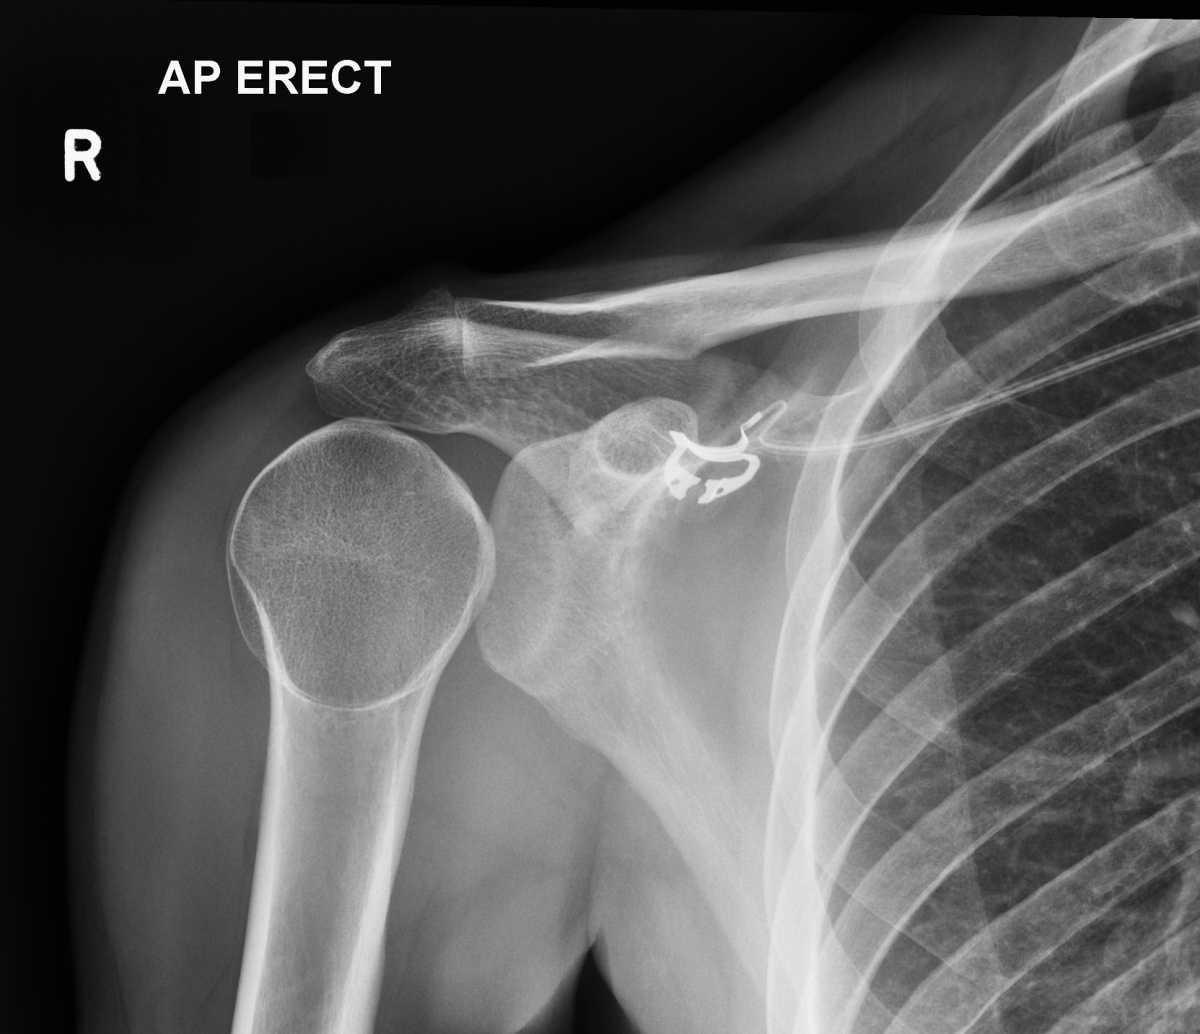

Aspect normal:

Matt A. Morgan, Radiopaedia.org. From the case rID: 85739